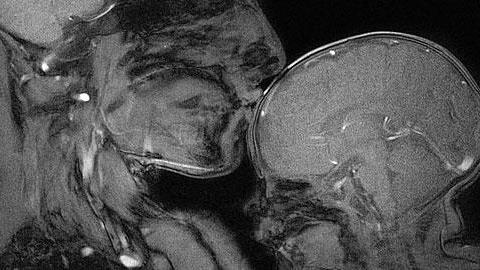

Μία μητέρα και καθηγήτρια νευρολογίας, αποφάσισε να αποτυπώσει τον ιδιαίτερο δεσμό που έχει κάθε μητέρα με το παιδί της μέσα από μία ακτινογραφία... εγκεφάλου. Το αποτέλεσμα θα σας καταπλήξει!